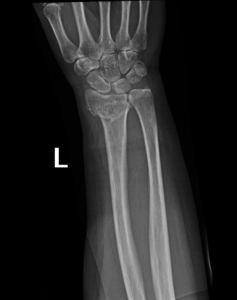

- Wrist Fractures.

Fractures can happen in a variety of ways. Most fractures are due to trauma, with others due to pathological conditions or overuse. Trauma can vary from high-energy injuries such as motor vehicle accidents to low energy injuries such as simple falls.

The human body heals fractures by forming a blood clot that calcifies, connecting the broken pieces of bone. For a good recovery, the bones must be held in the correct position and protected while healing occurs. This may be simply by a plaster or a cast.

if the fracture is displaced, surgery may be needed to put the bone back into the correct position and fix the bone with Plates & screws or nails for adequate healing to occur.